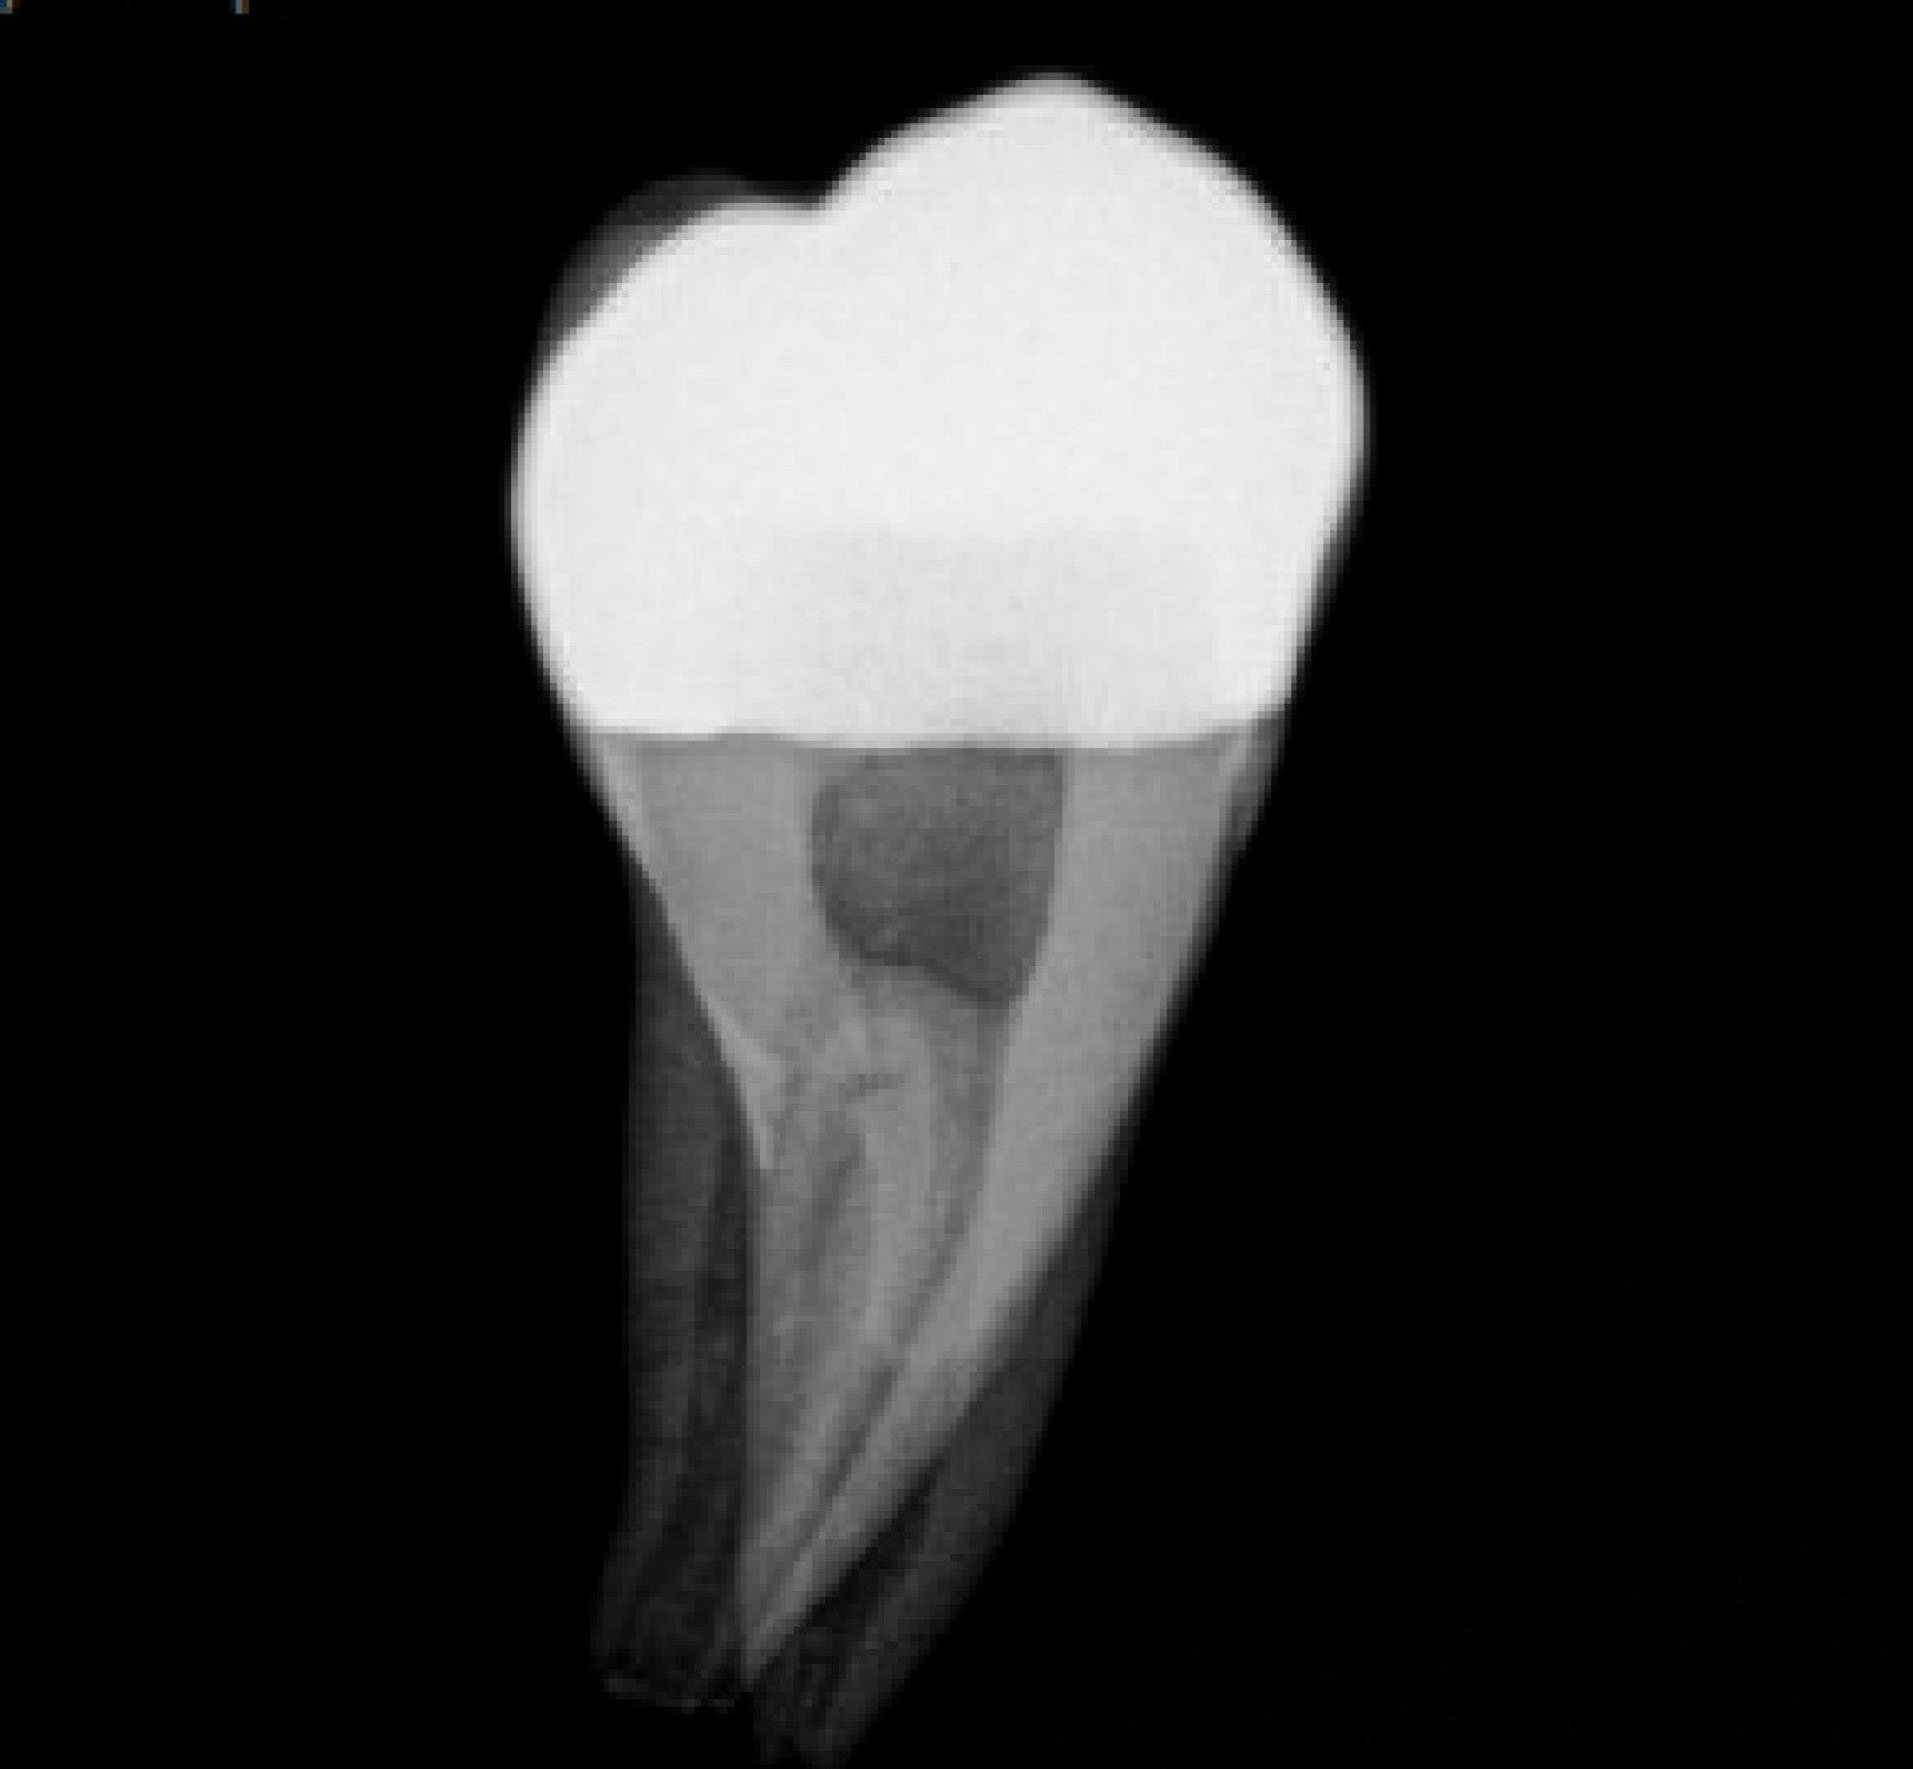

Each onlay was bonded to its corresponding prepared tooth using resin cement (GC, Alsip, United States) following the manufacturer’s protocol. 5 The restorations were then polished with high-speed diamond burs and slow-speed finishing discs. Post-cementation photographs were taken of the restorations in buccal, lingual, mesial, distal and occlusal views ( and ). Radiographs were also taken for each restoration in mesiodistal and buccolingual aspects ( and ).

joddd-15-147-g010

Figure 10. Buccal-lingual radiographic view of the cemented onlay.

The digital scanner provided an STL file of suitable resolution for three-dimensional (3D) printing in metal. The indirect onlay restorations were successfully 3D-printed in cobalt-chromium with dimensions, morphology, and fit clinically acceptable for subsequent cementation. Cementation was unremarkable and adequately retained the onlays, similar to previous investigations. 6 Marginal adaption was generally acceptable but was clinically unacceptable in one area due to an open margin. The surface finish was generally acceptable but could be improved in some areas, especially on the occlusal surface.